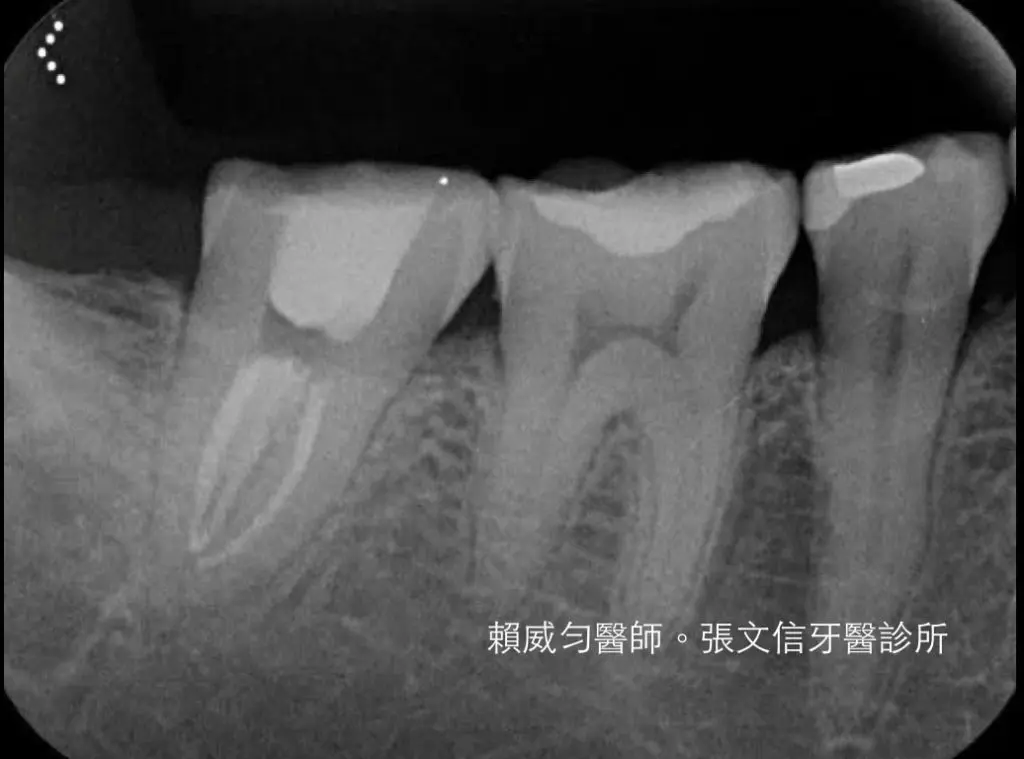

C-形根管是根管治療中大家都會遇到的困難案例。

C-形根管的開口多變,X光片的特徵容易讓人混淆,根管內部結構複雜,死角眾多。

賴威勻醫師,有一系列完美的C-形根管治療案例。賴威勻醫師是中山醫學大學 顯微根管總醫師,顯微根管臨床指導醫師。專門處理醫學中心裡,高難度的根管問題。